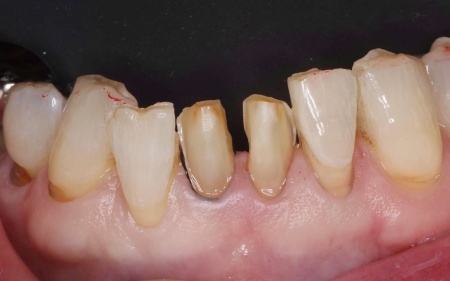

拝見したところ、下中央の前歯2本に長年の使用による色の変化やすり減り、小さな欠けが見られました。

すり減った部分は表面がざらつきやすくそこに着色が付きやすくなるため、患者様の場合も削れている部分が茶色く変色していました。

現時点では痛みや噛みにくさといった機能的な問題はなかったものの、このまま放置するとさらに歯がすり減り、将来的に痛みが出たり噛み合わせに影響が出たりする可能性も考えられます。

また患者様ご本人もお口を開けたときの見た目を気にされていたため、前歯の治療が必要と診断しました。